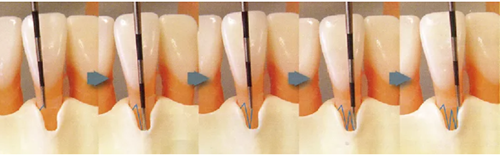

必知要點(diǎn)!注意到分界線

4點(diǎn)法和6點(diǎn)法都是將牙齒分區(qū)進(jìn)行檢測(cè)的,但是牙齒本身是沒有分界線的。

(如下圖所示,在腦中要有牙齒轉(zhuǎn)角處的線條印象。將拐角處的線條延伸至牙頸部紀(jì)委各區(qū)分界線。)

● 步行式牙周探診的操作

牙周探針的工作尖始終與牙體接觸,將工作尖從袋底上提1~2mm的幅度進(jìn)行步行式探診。